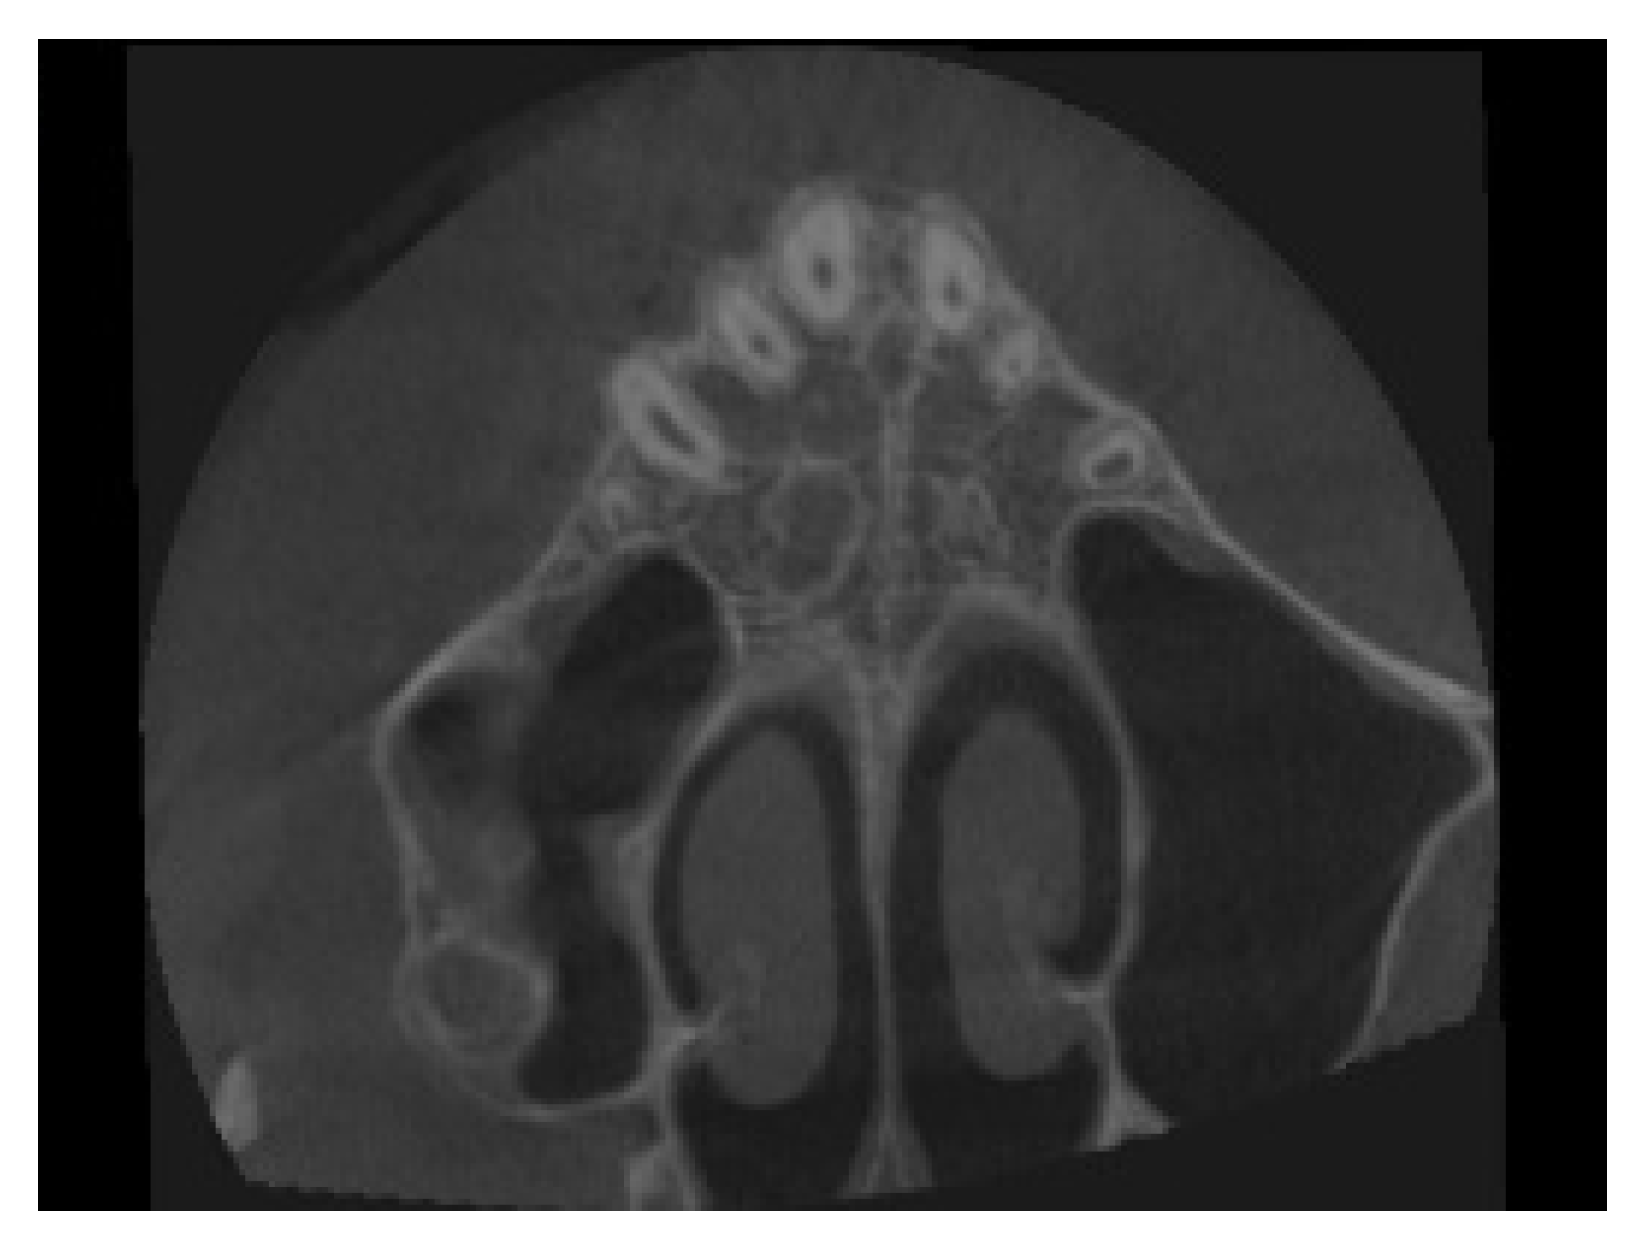

4. Case Report

4.1. Etiology and Diagnosis

4.3. Treatment Strategy

4.4. Treatment Progress